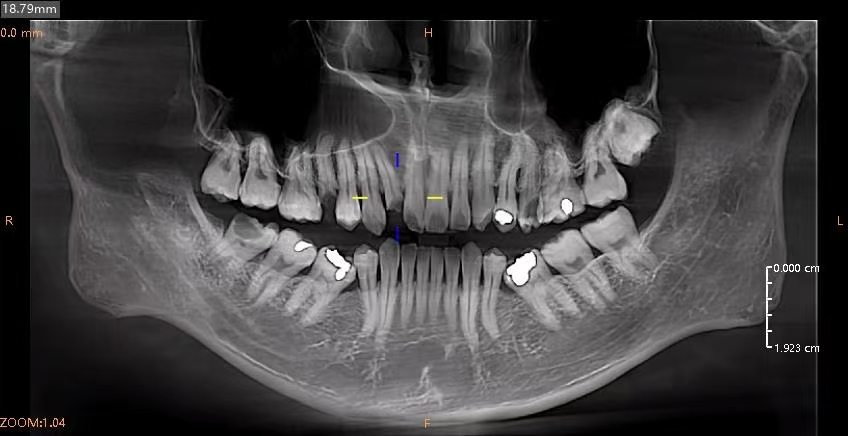

As a specialized masticatory organ, the tooth possesses dual sensory functions: first, the dental pulp nerve located within the pulp cavity, which can accurately perceive external stimuli such as sourness, sweetness, cold, and heat; second, the periodontal ligament surrounding the root surface, which is capable of sensitively detecting masticatory pressure and providing feedback to regulate occlusal force. When the dental pulp becomes infected and develops pulpitis, there is no need for hasty tooth extraction. Root canal therapy (RCT) is the preferred treatment modality for preserving the affected tooth. This procedure thoroughly removes the infected and necrotic pulp tissue, followed by disinfection and obturation of the root canal system, which can effectively eliminate pain and preserve the physiological functions of the tooth. Even though the treated tooth loses the ability to sense temperature and taste stimuli, the periodontal ligament can still normally transmit occlusal force signals, ensuring the fulfillment of masticatory functions. Clinical data indicate that with proper oral hygiene maintenance and necessary coronal restoration, the service life of teeth after root canal therapy can exceed 10 years, and some teeth can even maintain normal function for more than 20 years.

In contrast, dental implant restoration after tooth extraction can restore the masticatory hardness of the tooth, and the implant can form a stable osseointegration with the jawbone. However, dental implants have an inherent physiological limitation—they lack the pressure-sensing mechanism of the periodontal ligament. Patients cannot precisely control the magnitude of occlusal force during mastication; excessive occlusal force is prone to induce peri-implant bone resorption and loosening, ultimately leading to implant failure. In addition, the long-term survival of dental implants is highly dependent on rigorous postoperative maintenance, including professional cleaning care and regular follow-up examinations, making their maintenance significantly more challenging than that of natural teeth after root canal therapy.